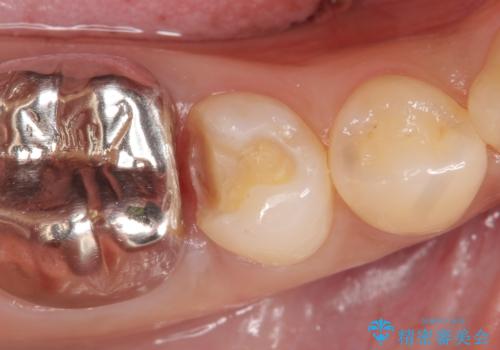

- 右下5番目の歯がしみるといらっしゃった方の症例です。

銀歯及び虫歯を除去し、適合に優れたPGA(ゴールド)インレーにて修復を行いました。